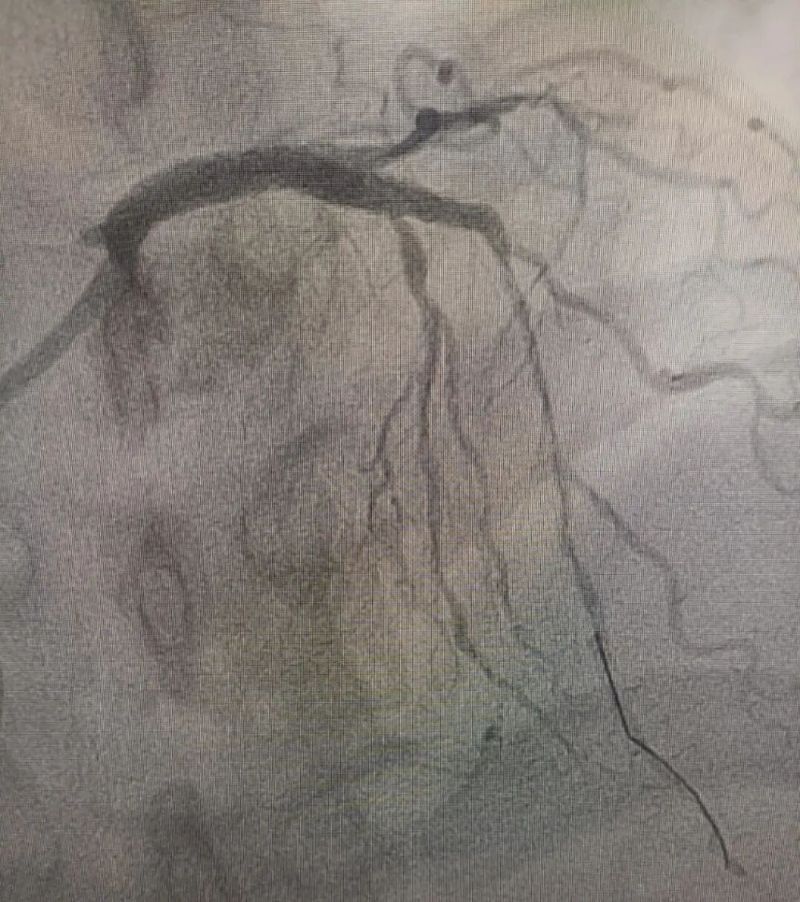

术中造影显示,左主干至前降支近段重度狭窄——这正是导致心脏缺血、诱发室颤的“罪魁祸首”。主动脉球囊反搏植入、球囊扩张、支架植入......介入团队精准操作,一气呵成。堵塞的血管顺利开通,血流重新涌动,这颗一度濒临停跳的心脏终于重获生机。

冠状动脉造影图

术后(左主干至前降支近段原狭窄消失)